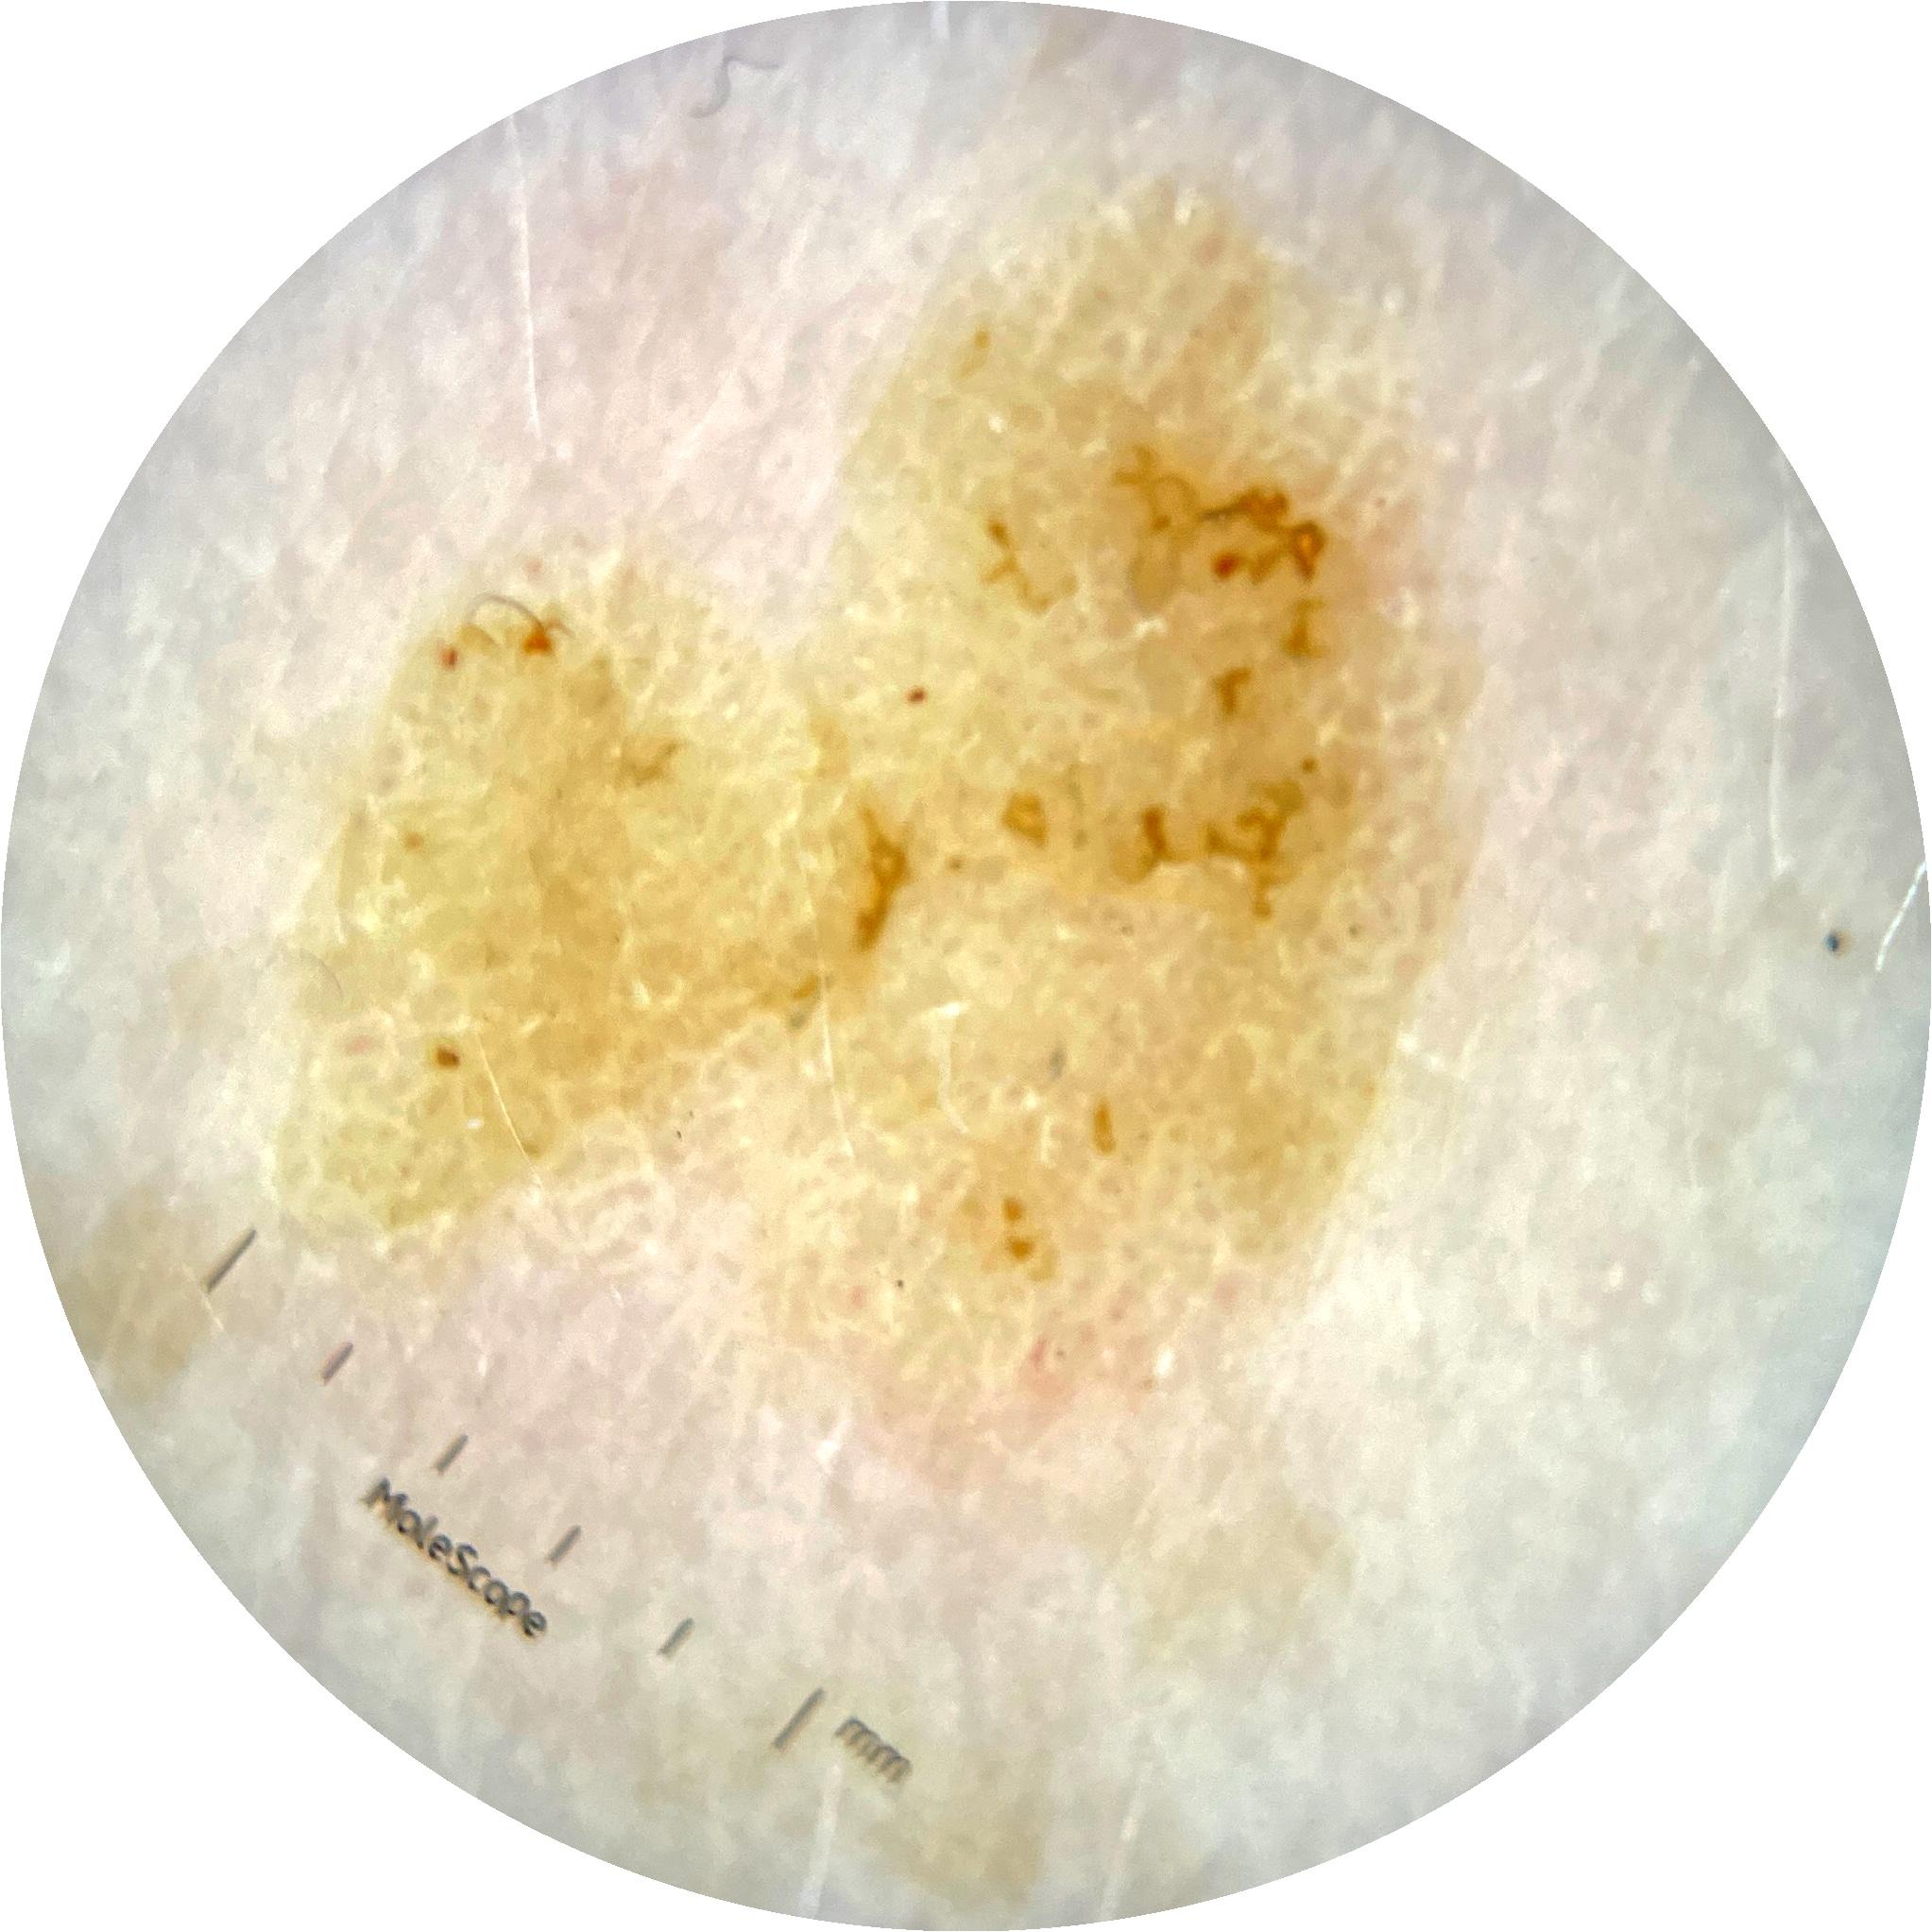

ISIC_9785574

Information

2003 x 2003

MEL-SELF Trial, https://www.sydney.edu.au/medicine-health/our-research/research-centres/melself-project.html

Field Value

acquisition_day 148

age_approx 45

anatom_site_1 Head and neck

anatom_site_general head/neck

concomitant_biopsy False

diagnosis_1 Benign

diagnosis_confirm_type single image expert consensus

family_hx_mm True

image_manipulation instrument only

image_type dermoscopic

lesion_id IL_0236417

patient_id IP_8456088

personal_hx_mm True

sex female